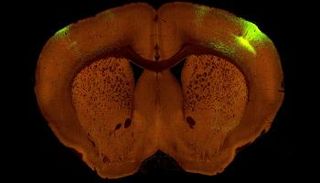

خريطة جديدة عالية الدقة لاتصالات الدماغ

الدراسة وضعت الأساس للباحثين لفهم أفضل للكيفية التي تتواصل بها دوائر الدماغ في الأمراض والاضطرابات مثل مرض ألزهايمر والفصام